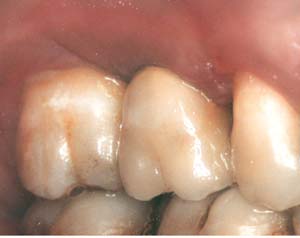

Second-stage surgery was performed after 4 months (Figure 8); healing abutments were placed and the soft tissue was allowed to heal for 5 more weeks. Then, splinted porcelain-fused-metal (PFM) crowns supported by custom gold abutments were delivered (Figure 9 and Figure 10).

Figure 9  Final implant-supported PFM restorations.

Figure 9